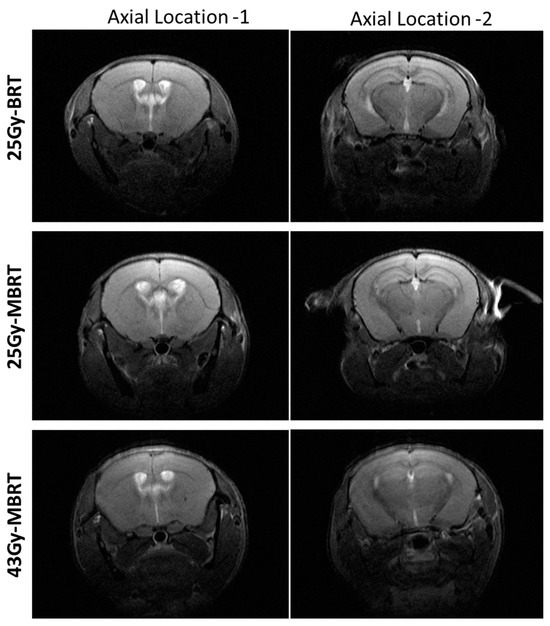

3.2. MRI Assessment